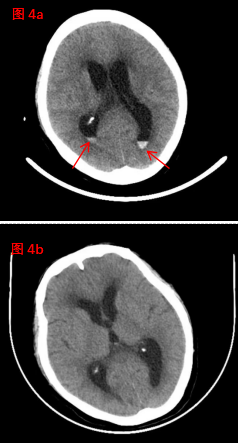

在神經(jīng)外科與腎病科的通力協(xié)作和精心救治下,患者精神狀態(tài)逐漸改善、飲食睡眠不斷好轉(zhuǎn),住院40天后,恢復良好,復查顱腦CT(圖4b)較入院時(圖4a,紅色箭頭處指示顱內(nèi)血腫)明顯吸收?;颊咝凶咦匀?,滿意出院!(神經(jīng)外科、宣傳科)